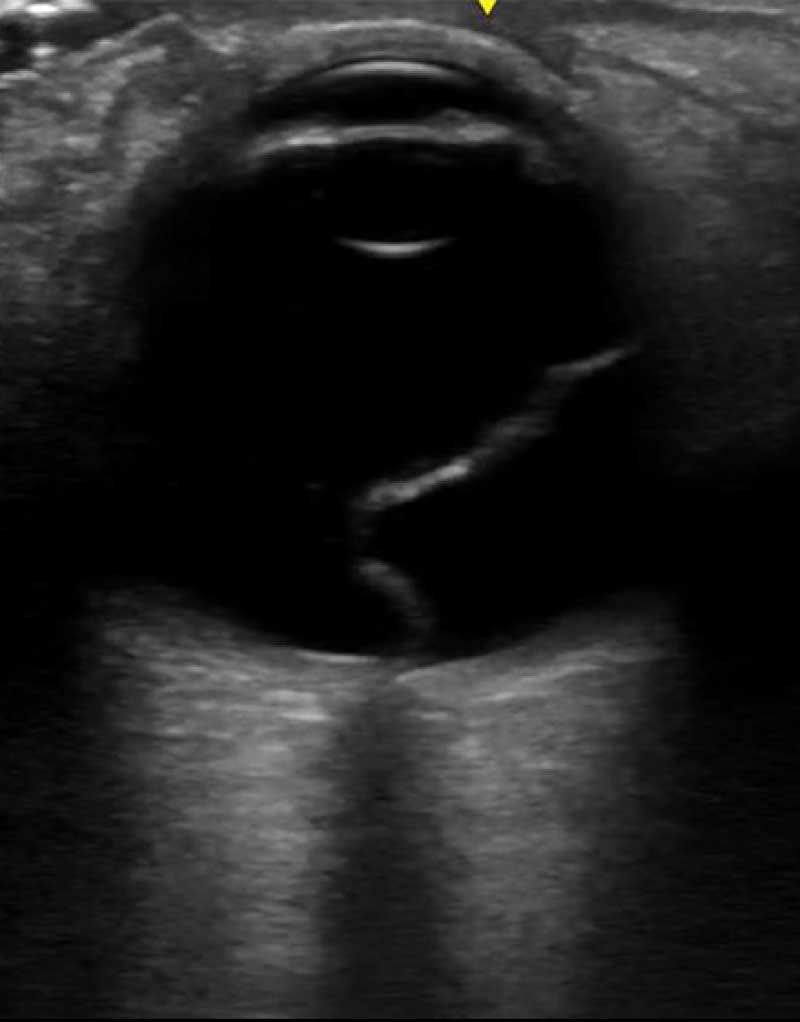

The retina is not usually visible. When it detaches, however, it becomes very conspicuous. The crucial thing to remember is that since it is an extension of the optic nerve, the two structures will always be attached. Detached retinas don’t float freely; they are tethered to the optic nerve. Vitreous detachments, on the other hand, are not anchored to the optic nerve. They do float freely.

With that in mind, it is clear why to differentiate the two on ultrasound, you MUST include the optic nerve on the scan. Also keep in mind that the ultrasound is a two dimensional slice of a three dimensional structure. If you do not visualize all the way through it, you will be fooled at times. It is essential that you sweep through the globe in two different planes and include the optic nerve.